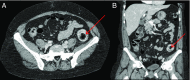

Intussusception typically occurs in infants and children, with adults representing 5% of cases. A 53-year-old African American woman presented with lower abdominal pain and tenderness. Computed tomography of the abdomen and pelvis demonstrated a 3.5 cm colocolonic intussusception in the descending colon. Emergent colonoscopy found solid stool in the mid descending colon. Water-soluble rectal enema showed a filling defect in the mid descending colon. Repeat colonoscopy demonstrated presence of a large fecaloma in left colon. Laxatives were initiated, and abdominal pain subsided. To our knowledge, this is the first report of colocolonic intussusception secondary to fecaloma.